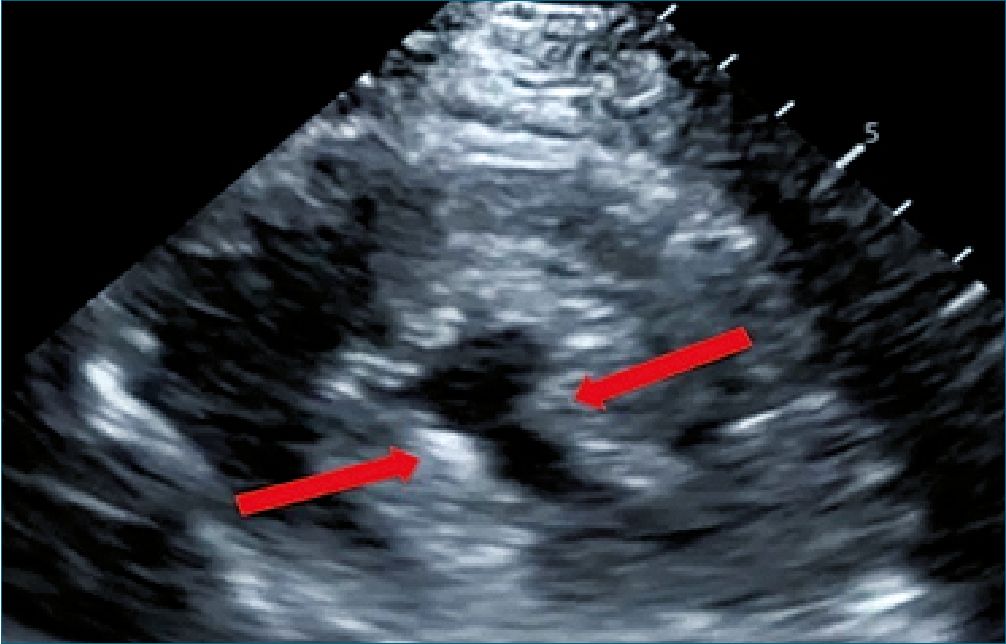

Figura 4. Eje corto paraesternal. Ventrículo izquierdo con colapso sis- tólico, con signo de los músculos papilares besándose como indica la flecha roja[20].

Además, en PSAX, la presencia del signo de los músculos papilares “besándose” o en PLAX (Figura 4), el contacto de velo anterior de la válvula mitral con el septum (Figura 5), apoyan la presencia de hipovolemia en contexto de sepsis, por lo cual está indicado la administración de fluidos guiado por metas. Debemos considerar que estos parámetros también dependen de la postcarga, motivo por el cual, a menor postcarga pueden presentarse incluso en ausencia de hipovolemia.